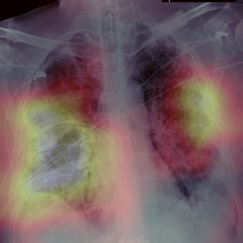

Early screening of patients is a critical issue in order to assess immediate and fast responses against the spread of COVID-19. The use of nasopharyngeal swabs has been considered the most viable approach; however, the result is not immediate or, in the case of fast exams, sufficiently accurate. Using Chest X-Ray (CXR) imaging for early screening potentially provides faster and more accurate response; however, diagnosing COVID from CXRs is hard and we should rely on deep learning support, whose decision process is, on the other hand, "black-boxed" and, for such reason, untrustworthy. We propose an explainable two-step diagnostic approach, where we first detect known pathologies (anomalies) in the lungs, on top of which we diagnose the illness. Our approach achieves promising performance in COVID detection, compatible with expert human radiologists. All of our experiments have been carried out bearing in mind that, especially for clinical applications, explainability plays a major role for building trust in machine learning algorithms.